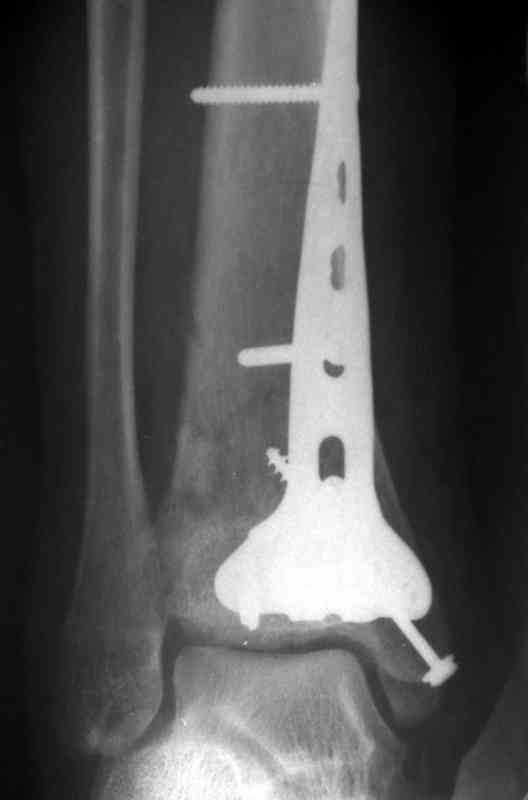

На рентгенограммах типичный перелом пилона по типу С-3. есть опыт до 100 открытых опреаций у нас в клинике. 20 примерно в год. Принцип один -все внутрисуставные переломы нуждаются в открытой репозиции и внутренней стабильной фиксации. При поступлении КТ не надо, так как получается только нагромождение костей. Истинной картины нет. Главное восстановить длину малоберцовой кости - это ключ к успеху. При поступлении меньше всего надо думать о сосудистых расстройствах, т.к. сама операция и репозиция даже сначала частичная даёт улучшение сосудитых нарушений. Причём очень быстро. Операция в 2этапа. При поступлении доступ позади наружной лодыжки, причём обязательно. После этого репозиция малоберцовой кости и фиксация пластиной 1/3 трубки под винт 3,5. Дренаж и любой аппарат наружной фиксации. Затем после спадения отёка на 5-7-10 день аппрат снимается и дугообразный разрез спереди от медиальной лодыжки 10-12 см. Главной чтобы расстояние между 1 и вторым разрезом было не меньше 7-8 см. Тогда не будет некрозов лоскутов. Таранная кость используется как матрица на неё укладываются отломки и фиксируются пицами. Ренг-контроль. Отломки лежат все отдельно, но ничего не высыпется. При переломах С-3 всегда нужна костная пластика (из крыла). Фиксация пластиной лист клевера простой или LCP. Гипс не нужен. Дренаж до 48 часов. Операция длится 3-4 часа обязательно без жгута. Посылаю примерно такой же случай.

Ещё есть одна проблема когда есть перелом малоберцовой кость, то всё ясно. А когда малоберцовая кость не повреждена, то сразу накладывается аппрат наружной фиксации при поступлении, чтобы как бы перерастянуть отломки и главное убрать вальгусное или варусное смещение, а потом на 5-7 день открыто большеберцовая кость восстанавливается и фиксируется пластиной. С уважением Дрягин

Послала ещё два снимка, если не пройдут, пошлю ещё. Дрягин. Если есть вопросы, готов ответить.